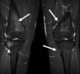

Osteonecrosis of the distal tibial epiphysis

Osteochondritis dissecans (OCD or OD) is a joint disorder primarily of the subchondral bone in which cracks form in the articular cartilage and the underlying subchondral bone. OCD usually causes pain during and after sports. [Source: Wikipedia ]